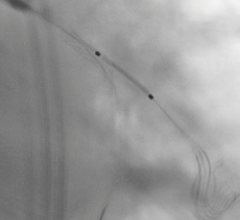

November 1, 2013 — A new clinical trial showed that a two-stent technique for treatment of bifurcation lesions with a ...